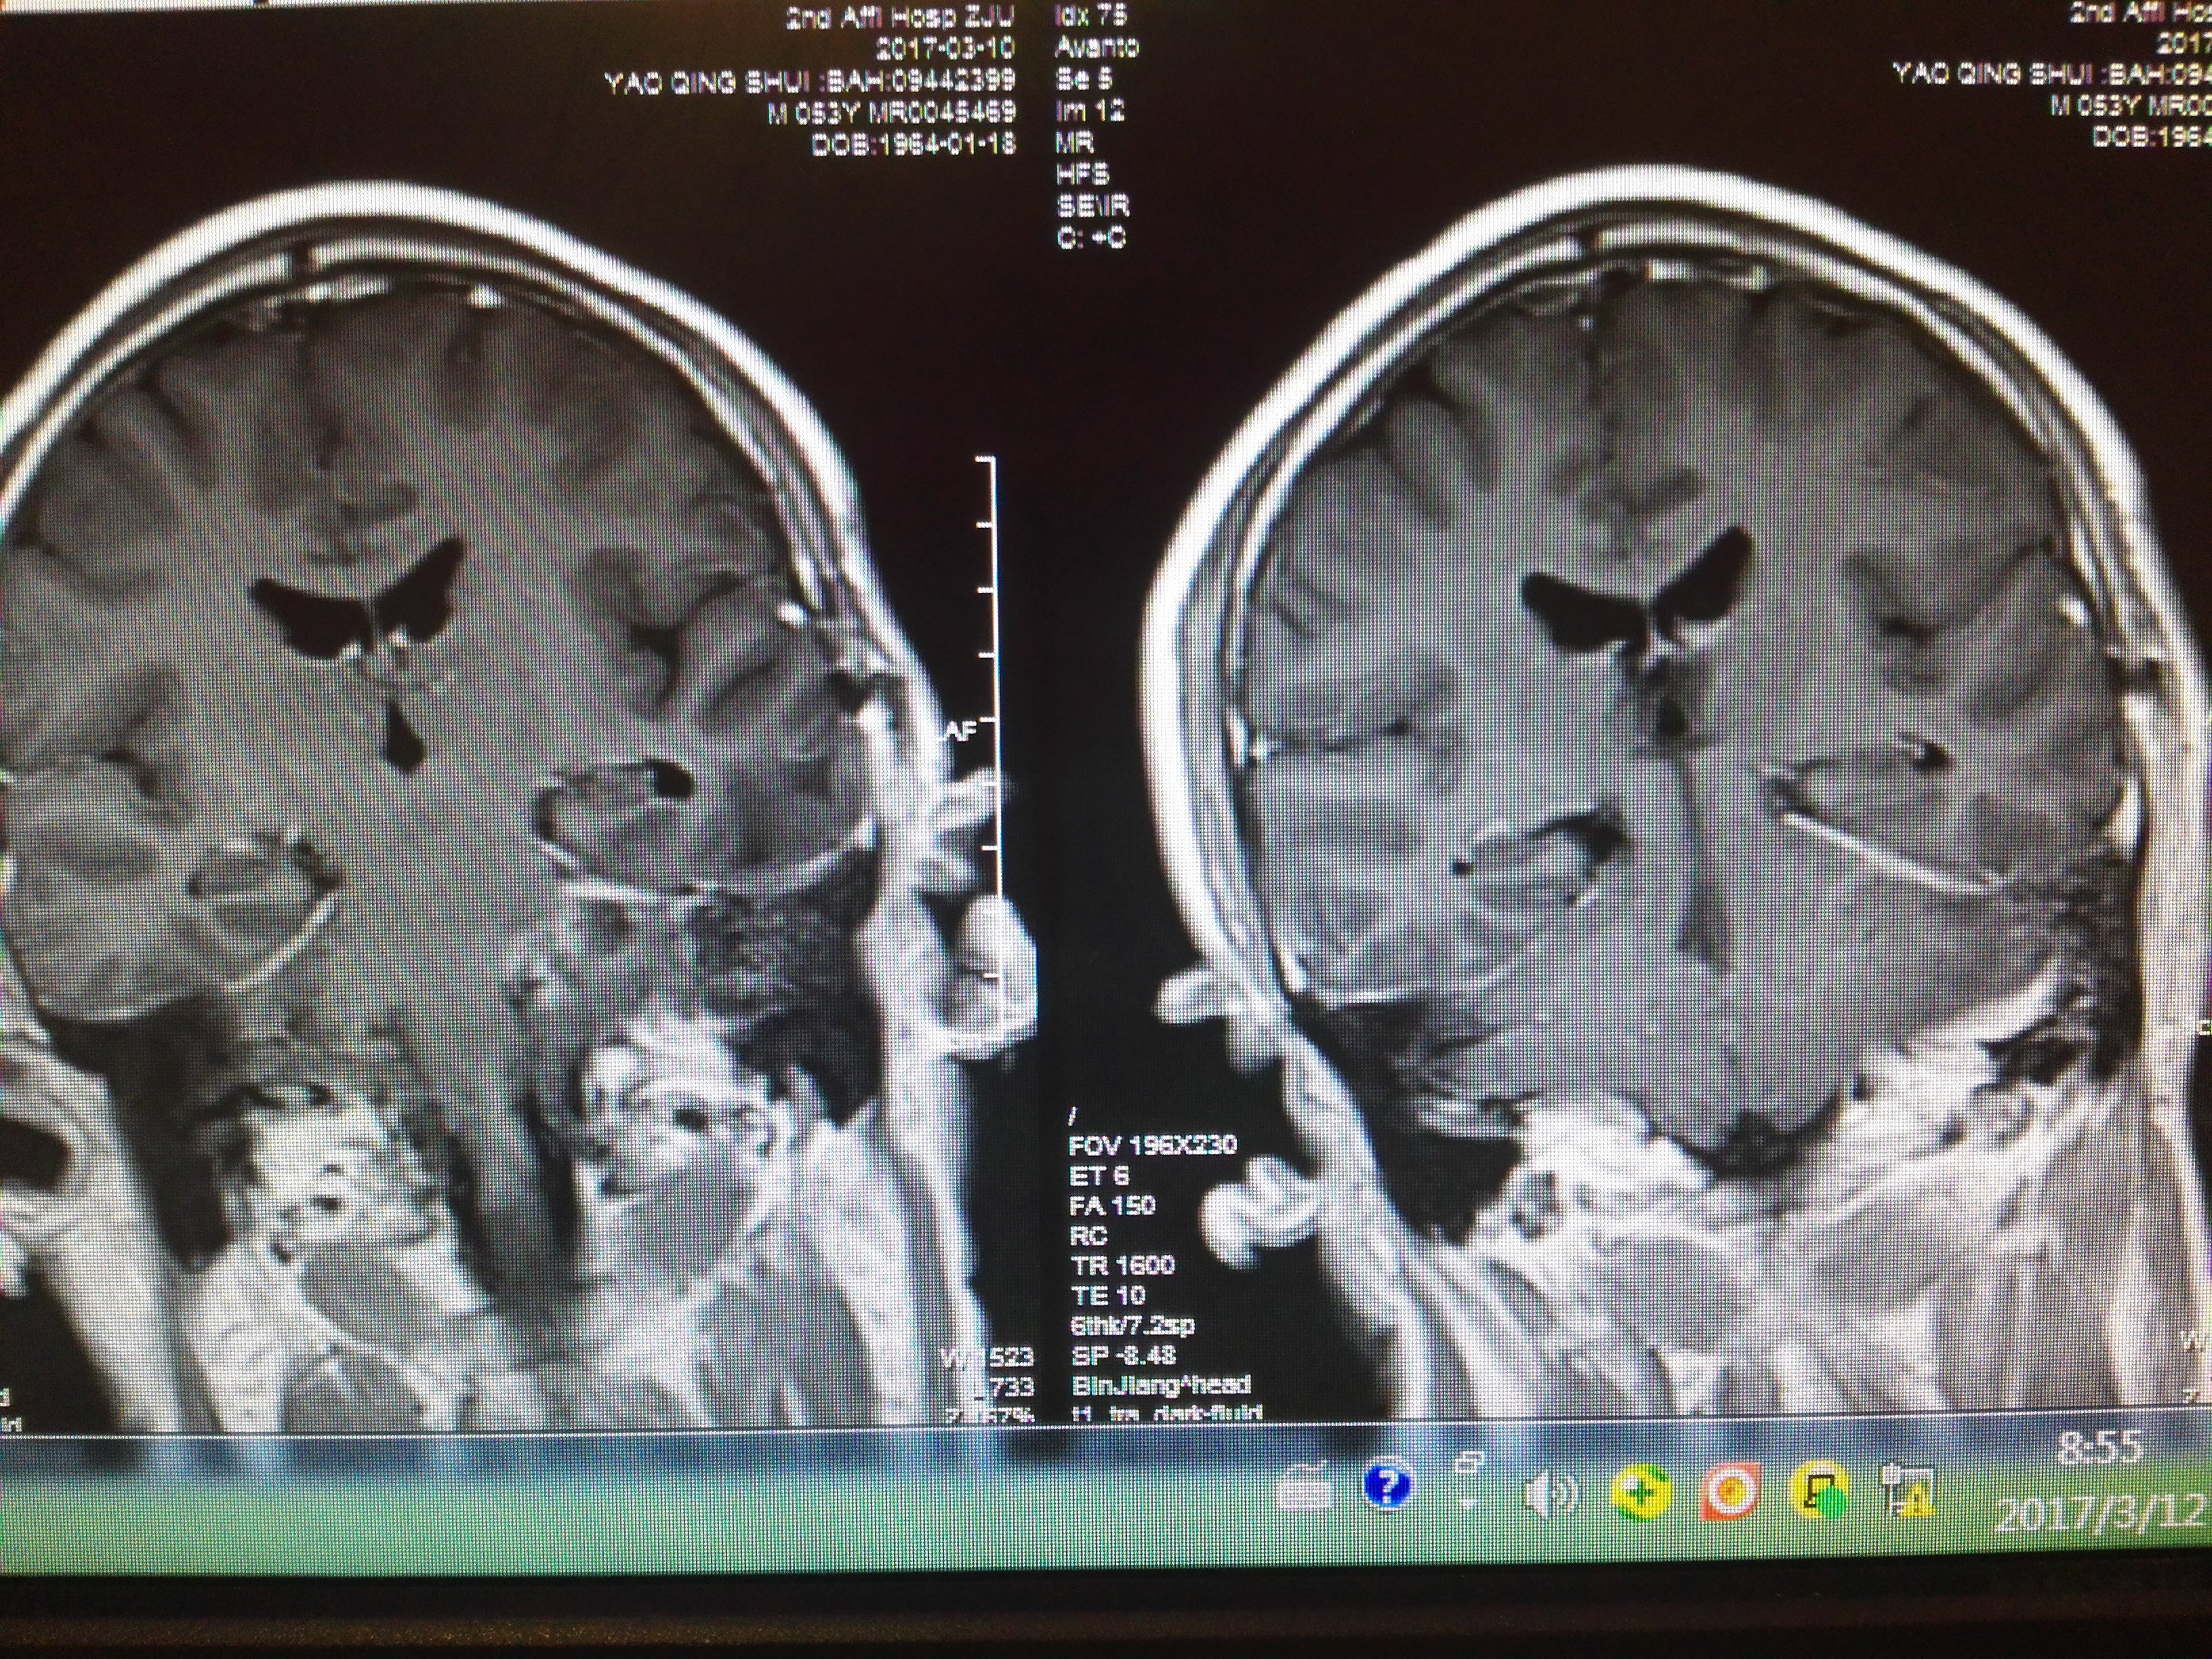

巨大骑跨中后颅窝哑铃型神经鞘瘤全切治疗 - 好大夫在线

图片尺寸3264x2448